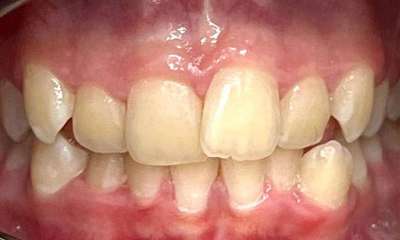

This patient was worried about the incisal edges of her front teeth that had become thin and prone to chipping. This had started in her twenties and unfortunately, now in her thirties, was progressing due to her deep and tight bite and minor crowding.

In her case, Dr Gourlay used 14 series of Invisalign aligners over 14 weeks to align her teeth into a more protected bite pattern. She then used composite bonding to restore the chipped edges. The patient has since moved on to using retainers at night to maintain and protect the position of the teeth.